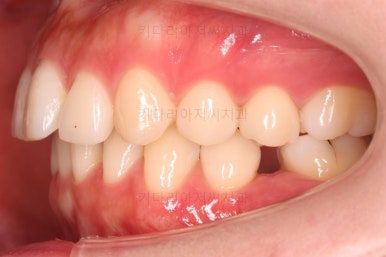

공간, 교합, 중앙선 모두 매우 좋아지고 있습니다.

윗니 한 쪽만 왜소치여서 100% 중앙선을 못맞추는 건 환자분 본인도 잘 아시는데요.

그래도 할 수 있는데까지 해보기로 했습니다.

중앙선도 처음보다 매우 좋아진 양상입니다.

옆모습도 큰 변화없이 양호하게 진행중이고요.